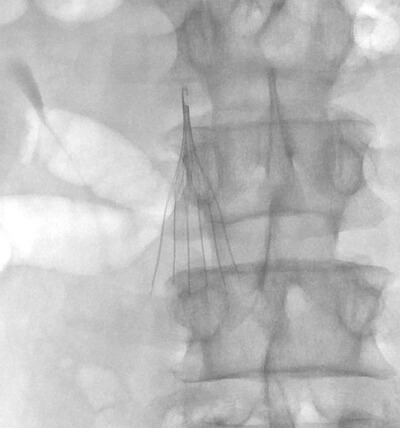

The IVC filter placement procedure first involves placing a small catheter tube into a patient’s vein. We most commonly access the right or left common femoral vein in the groin or the right internal jugular vein in the neck to place a filter. However, other veins such as a small vein of the arm or the popliteal vein behind the knee can be used for filter placement as well. Once a small catheter is placed into the vein, it is directed into the Inferior Vena Cava (IVC). Contrast, or x-ray dye, is injected into this catheter, and images of the Inferior Vena Cava are obtained. These images allow us to determine the size of the IVC, whether clot is present within the IVC, whether the IVC is normal in appearance or if there is a congenital variation present which may impact filter placement, and where the renal veins enter the IVC (since that determines where the filter is placed within the IVC). Once all of this information has been obtained, we proceed to filter placement. This simply involves placing the filter, which is attached to a wire, into the catheter and positioning it appropriately within the IVC. Once the filter is where it needs to be, it is released from the wire and deployed in the vein.